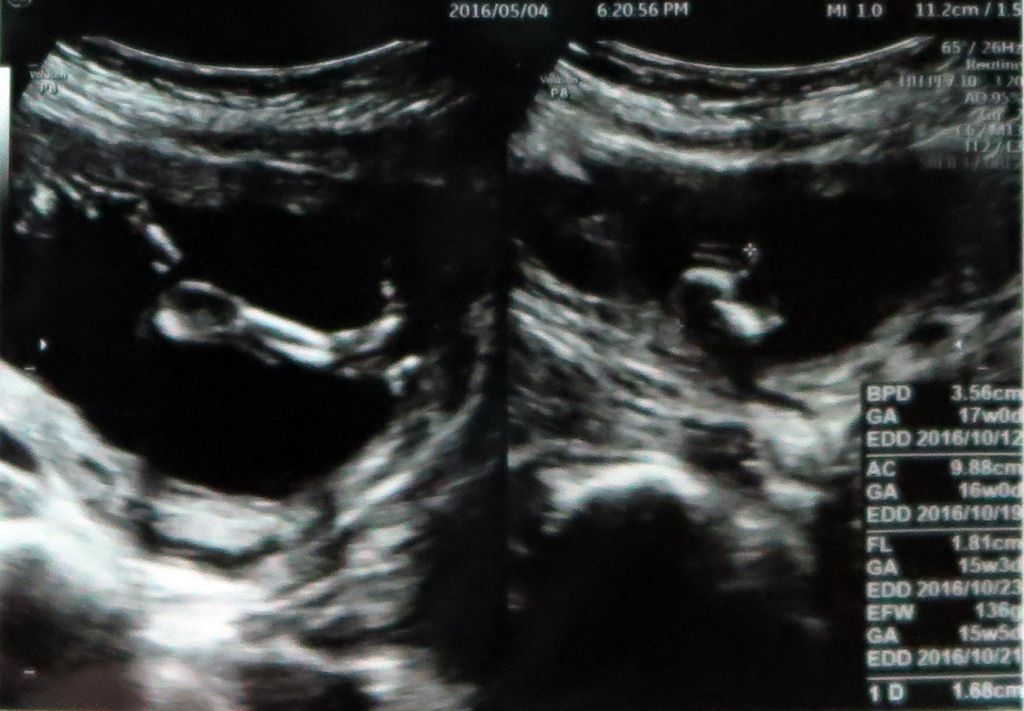

아주 잘크고 있답니다. 크기도 주차에 맞게 커가고 있고 (머리는 1주 더 크다는데.ㅠㅠ 똑똑한 아이겠죠?ㅎㅎ)

몸무게는 136g, 키가 16cm에 발은 1.68cm정도 된답니다.

다른건 다 있고 가운데 불필요한건 없다네요..ㅋㅋ

원하던 딸이라는 소식에 두배로 행복합니다.